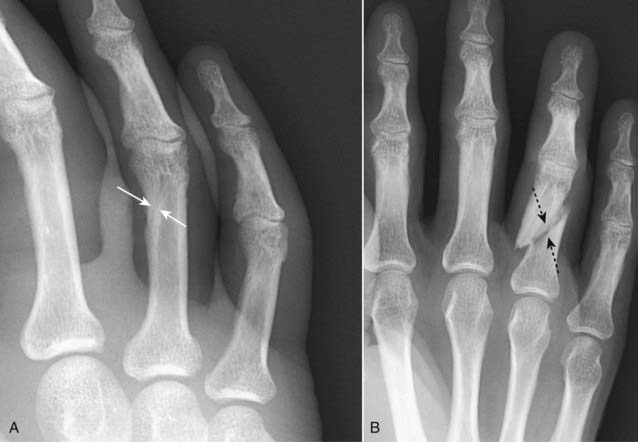

image Jones fracture is a transverse fracture of the 5th metatarsal about 1 to 2 cm from its base caused by plantar flexion of the foot and inversion of the ankle. A Jones fracture may take longer to heal than the more common avulsion fracture of the base of the 5th metatarsal (Fig. 22-23).

Figure 22-23 Jones fracture, base of 5th metatarsal.

A Jones fracture is a transverse fracture of the base 5th metatarsal (dotted white arrow). It occurs about 1 to 2 cm from the tuberosity of the 5th metatarsal (solid white arrow) and frequently takes longer to heal than an avulsion fracture of the tuberosity. It is caused by plantar flexion of the foot and inversion of the ankle.